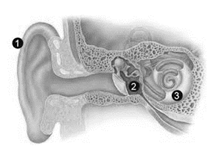

Observe a imagem abaixo.

Em relação a estrutura do sistema auditivo podemos afirmar, que:

I. a entrada de sons no canal auditivo faz com que a membrana timpânica se mova.

II. as vibrações sonoras se movem através da cóclea para os ossículos.

III. na imagem, o nº1, corresponde ao pavilhão auditivo, a nº2 tímpano e a nº3 ouvido interno.

IV. a cóclea é um canal espiral ósseo que está dividido e localizado no interior do osso temporal.

V. a janela redonda é a entrada para orelha interna, localizada junto à base da rampa vestibular.

É CORRETO o que se afirma em: